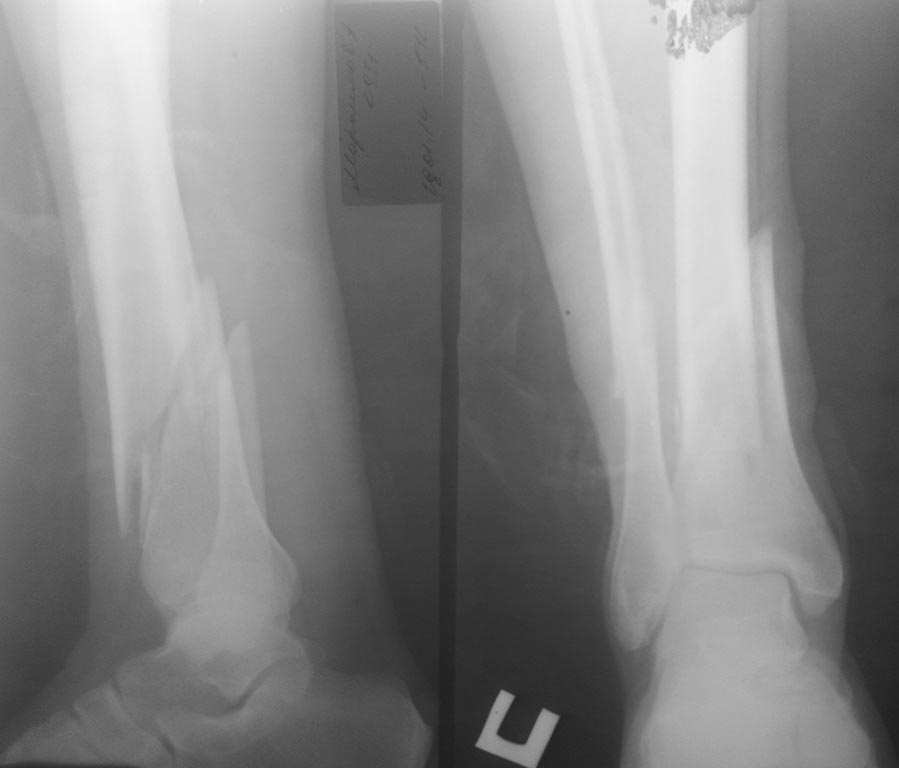

Коллеги, поступил пациент 63 г, с диагнозом: Открытый оскольчатый перелом нижний трети костей голени. Упал с высотой 3 метра, рана по медиальной поверхности 1,0 х 0,5 см, без признаков воспаления.Таких переломов синтезировали аппаратом Илизарова или накостными пластинами. В данном случае можно ли фиксировать блокирующим стерженем и интраоперационно какие трудности возникает?

Здравствуйте! Сделайте КТ, чтобы убедиться, что нет расколов в сустав, если нет, можно и БИОС, тогда максимум винтов дистальных и правильное положение в голеностопном суставе. Удачи!

Добрый вечер. Стержнем синтезировать можно, но необходимо не менее трех дистальных блокируемых винтов в разных плоскостях, верхушку гвоздя расположите как можно ближе к суставу. С целью облегчения репозиции наложите дистрактор и введите поллерный винт в сагитальной плоскости дистального отломка.

Интрамедуллярный остеосинтез здесь возможен. Вариантов техники много. Мы предпочитаем спицевой дистрактор. Дистальную спицу можно провести за таран. Наружную лодыжку до дистракции 1-2 спицами пришпилить к тарану.

Если намерены пользоваться тракционным столом, для управления варусом-вальгусом можно сделать джойстик, стержень 5-6 мм во фронтальной плоскости близко к суставу.

Кстати, если по КТ есть линии раскалывания в сустав, то стоило бы ввести несколько спиц субхондрально, чтобы не разобщить фрагменты, и для этого же перед введением гвоздя сформировать для него ложе разверткой. Хотя это более актаульно для молодых, с прочной и плотной костью.

В периферическом отломке гвоздь должен идти параллельно и ближе к латеральной стенке. Действительно, для этого можно ввести спереди назад 1-2 спицы, можно "лесенкой". Кончик гвоздя должен быть не напротив середины таранной кости, а на границе средней и наружной трети ее видимого поперечника.